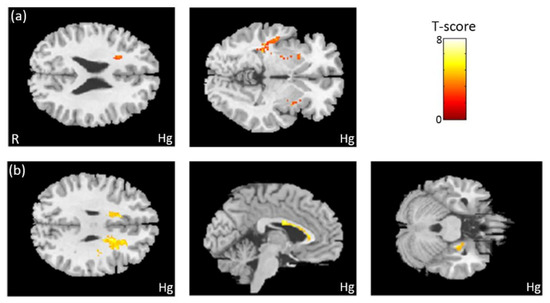

3.7. The Association Between Heavy Metals and GQI